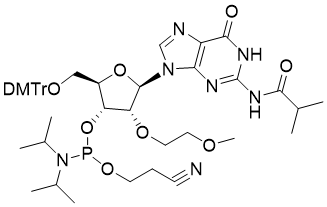

馬鞍山致研生物醫(yī)藥科技有限公司成立于馬鞍山市鄭浦港新區(qū)現(xiàn)代產(chǎn)業(yè)園。公司專(zhuān)注于生物小分子、醫(yī)藥中間體相關(guān)產(chǎn)品的研發(fā)和生產(chǎn),產(chǎn)品主要包括DNA亞磷酰胺單體、RNA亞磷酰胺單體、特殊單體以及按照客戶(hù)要求定制的RNA和DNA,并且公司提供定制合成等方面的研究服...

馬鞍山致研生物醫(yī)藥科技有限公司成立于馬鞍山市鄭浦港新區(qū)現(xiàn)代產(chǎn)業(yè)園。公司專(zhuān)注于生物小分子、醫(yī)藥中間體相關(guān)產(chǎn)品的研發(fā)和生產(chǎn),產(chǎn)品主要包括DNA亞磷酰胺單體、RNA亞磷酰胺單體、特殊單體以及按照客戶(hù)要求定制的RNA和DNA,并且公司提供定制合成等方面的研究服...